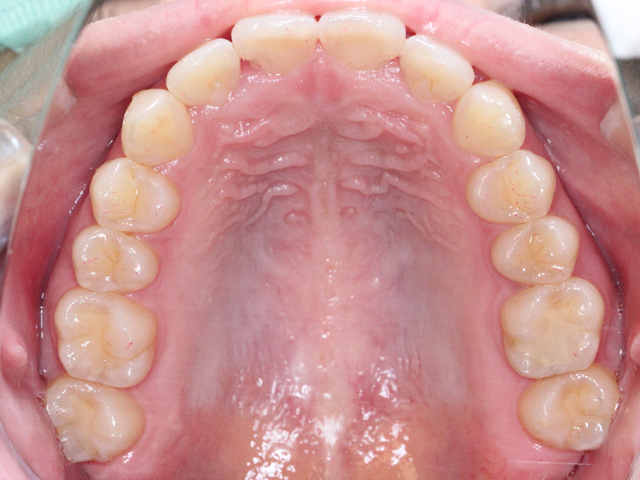

上顎の画像です。前歯のスペースが不足しています。

中切歯が押し出されているように見える状態です。また右上の中切歯は専門用語で「捻転(ねんてん)」と呼ばれる、歯が捻じれている状態です。

正中の中心に向かって捻じれている「近心捻転(きんしんねんてん)」と呼ばれる状態です。